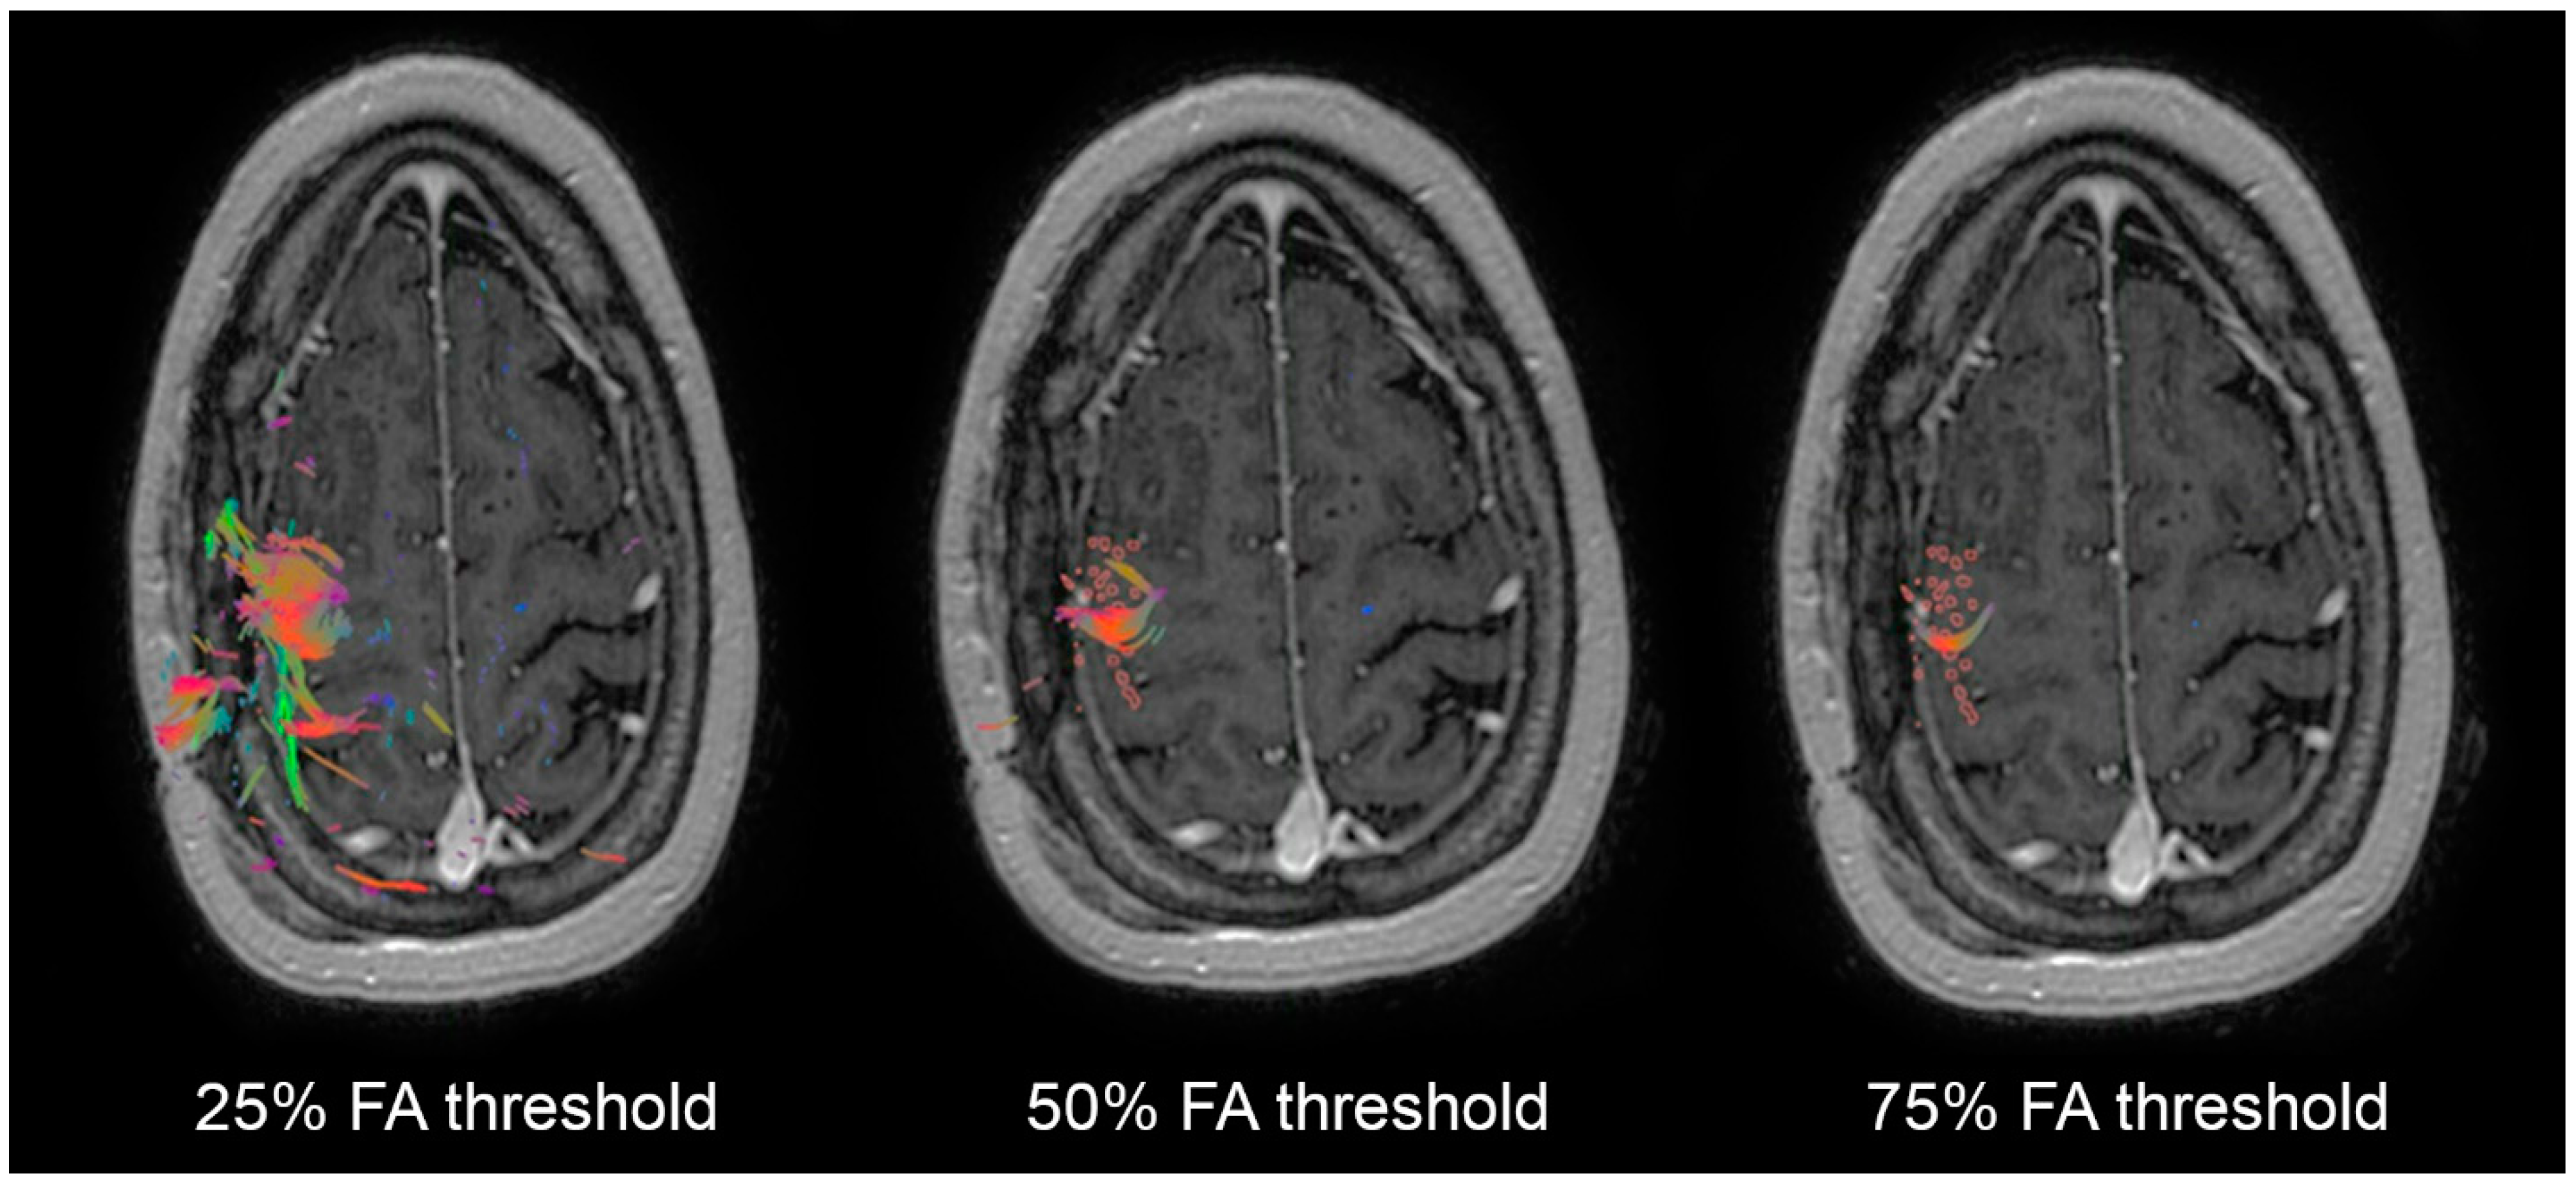

| Tractography at 25% FA | Deficit | No Deficit | Tractography at 50% FA | Deficit | No Deficit | Tractography at 75% FA | Deficit | No Deficit |

|---|---|---|---|---|---|---|---|---|

| Resection | 6 | 15 | Resection | 6 | 6 | Resection | 6 | 1 |

| Preservation | 1 | 29 | Preservation | 1 | 29 | Preservation | 1 | 34 |

| No. of Patients | Permanent Deficits, No. (%) | OR | 95% CI | p Value | |

|---|---|---|---|---|---|

| Resection of 25% FAT TMS WMTs | |||||

| Yes | 21 | 6 (29%) | 8 | 0.87–73.68 | 0.066 |

| No | 21 | 1 (4.8%) | |||

| Resection of 50% FAT TMS WMTs | |||||

| Yes | 12 | 6 (50%) | 29 | 2.93–287.02 | 0.004 |

| No | 29 | 1 (3.4%) | |||

| Resection of 75% FAT TMS WMTs | |||||

| Yes | 7 | 6 (86%) | 204 | 11.17– 3724.26 | <0.0001 |

| No | 35 | 1 (2.9%) |